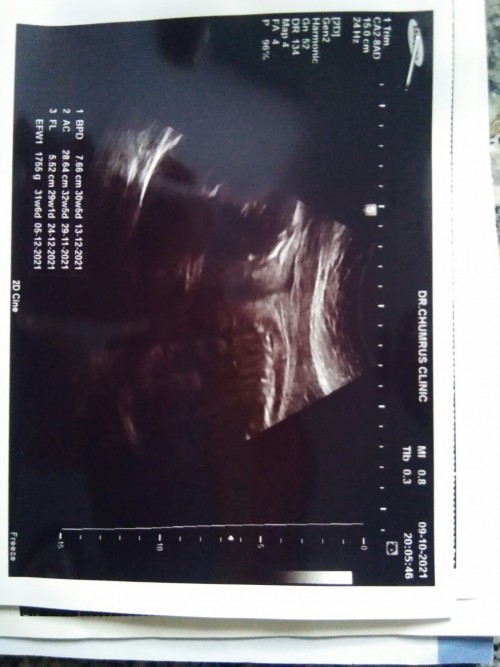

บ้านนี้ลูกสาวคะ. 19ธ.ค 64